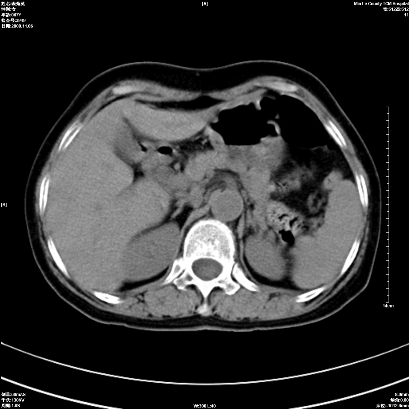

以下是引用卜一在2008-11-6 15:58:00的发言:[br]胰头略增大,胆总管扩张,末端渐行性狭窄。多考虑:胰头癌!建议增强!